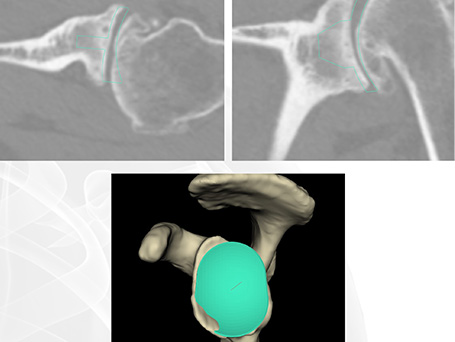

Zur Vorbereitung der Operation legen wir spezielle CT Untersuchungen an, um nach Analyse des Gelenkes eine genaue Planung zu ermöglichen. Dabei wird in allen Ebenen die Abnutzung des Gelenkes, etwaige Knochendefekte und die aktuelle Stellung der Gelenkpartner zueinander analysiert. Diese Planung führt durch die dreidimensionale Analyse der patienteneigenen Anatomie und eine Bewegungssimulation im Computer mit eingesetzten Implantaten zu einer sehr genauen Planung der Operation.

Deutliche rechtsseitige Omarthrose (Schultergelenksverschleiß) mit dorsalem knöchernem Pfannendefekt in der dreidimensionalen präoperativen Planung. Operative Behandlung mit einem Knochenaufbau (BIO RSA) über den körpereignen Knochen aus dem Oberarmkopf und einem Inversen künstlichen Schultergelenk mit kurzem Schaft.

Primäre Omarthrose einer 84-jährigen Patientin auf der rechten Seite mit einem sich im 3D-CT darstellenden B2 Glenoid nach Walsh. Versorgung nach präoperativer virtueller Planung mit einer zementfreien Inversen Prothese. Alltagstaugliches Ergebnis mit Wiedergewinnung der Eigenständigkeit insbesondere auch in der Pflege ihrer eigenen Haare.